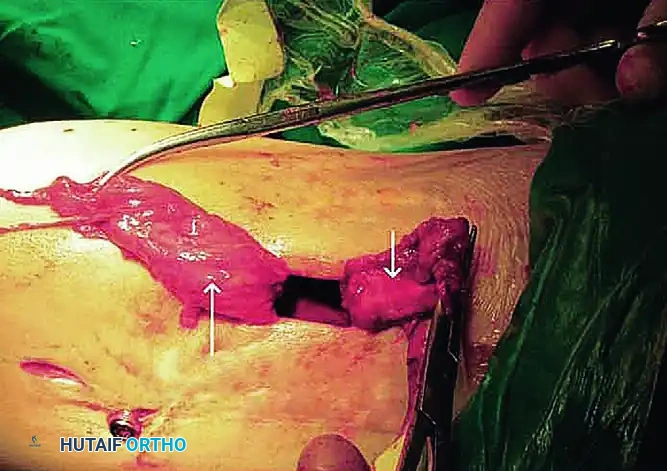

4. Excision of the Vastus Intermedius

This is the critical step of the Thompson procedure. The vastus intermedius will typically present as a dense, scarred band binding the rectus femoris and patella to the femur.

- Excise the vastus intermedius completely.

- Crucial Step: Leave a thin fibrous or periosteal covering on the anterior surface of the femur to prevent raw cortical bone from adhering to the rectus femoris postoperatively.

Surgical Warning: If the tendon of the rectus femoris has been destroyed by the initial injury or previous surgeries, the surgeon must create a neo-tendon by making longitudinal incisions through the dense scar tissue in the distal third of the thigh.

- Separate the tendinous tissue of the vastus intermedius from the posterior surface of the rectus femoris and the anterior surface of the femur.

- If flexion remains inadequate after the first three stages, proceed to Stage 4.

- Transect the previously mobilized vastus intermedius at a level near its musculotendinous junction. In knees with moderate arthrofibrosis, these first four stages often allow knee flexion of more than 120 degrees, at which point the procedure can be terminated.